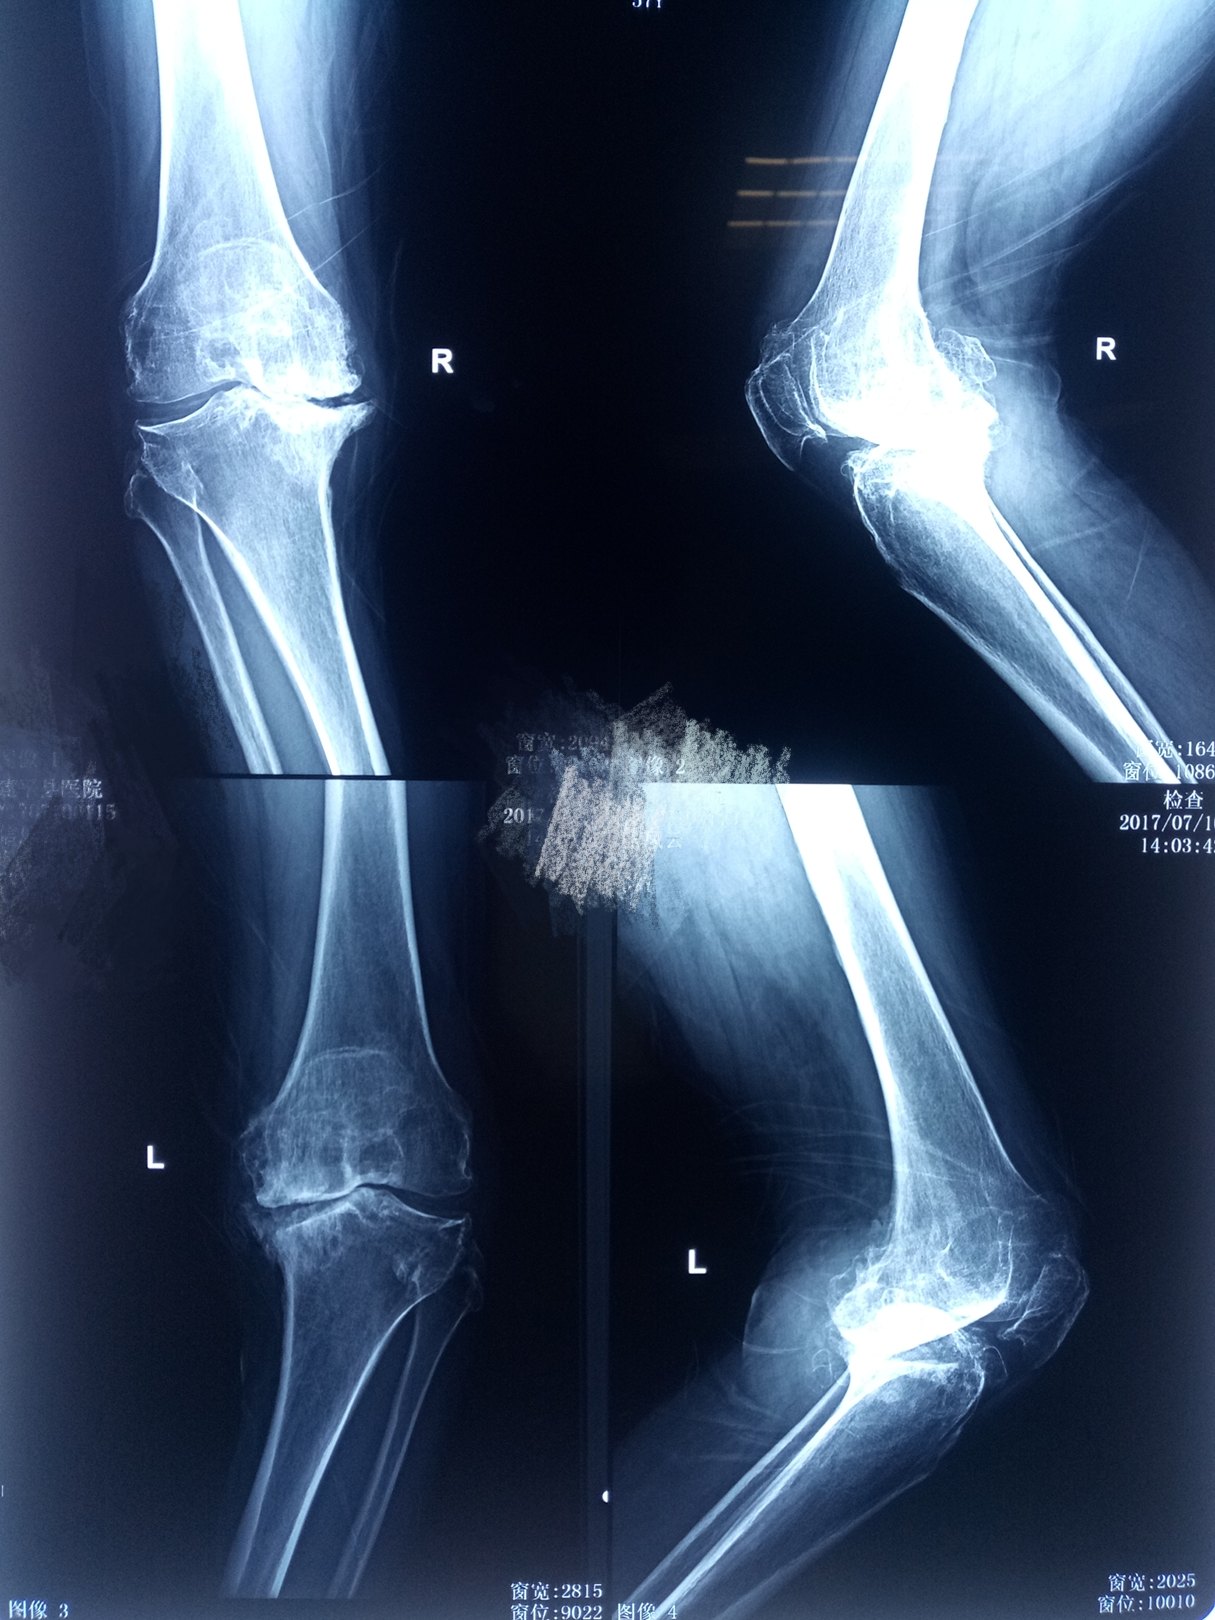

类风湿关节炎双膝破坏

图片尺寸2085x1689